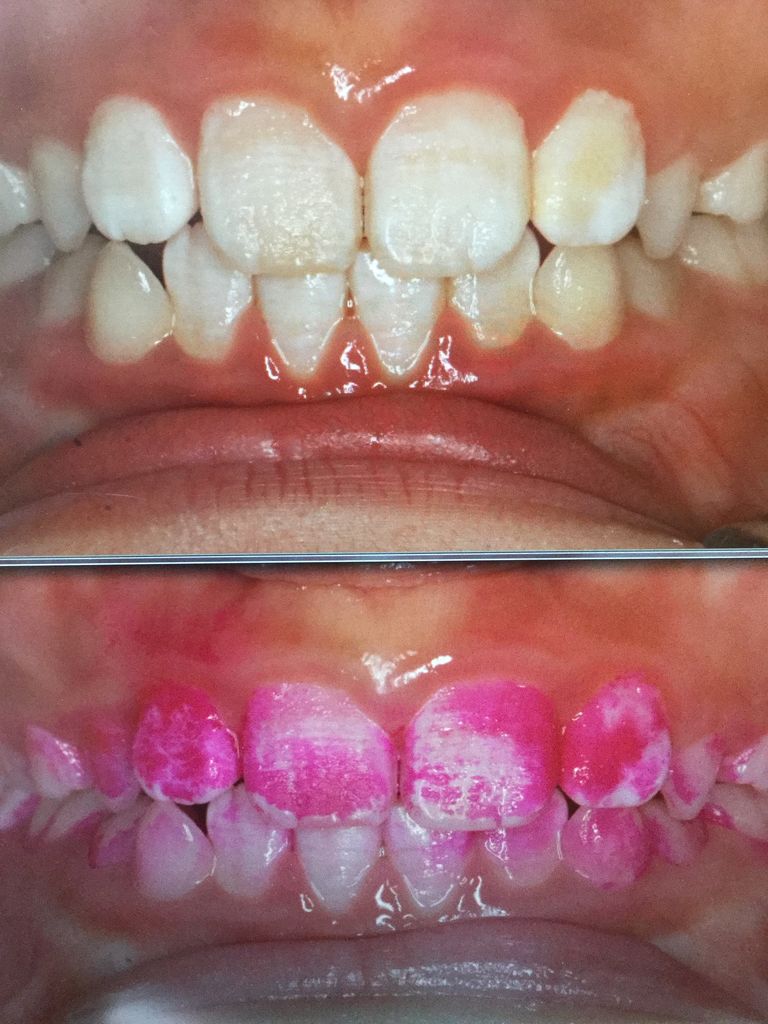

¥×¥é¡¼¥¯¥³¥ó¥È¥í¡¼¥ë¤Î¼£ÎÅÃæ¤Ç¤¹¡£